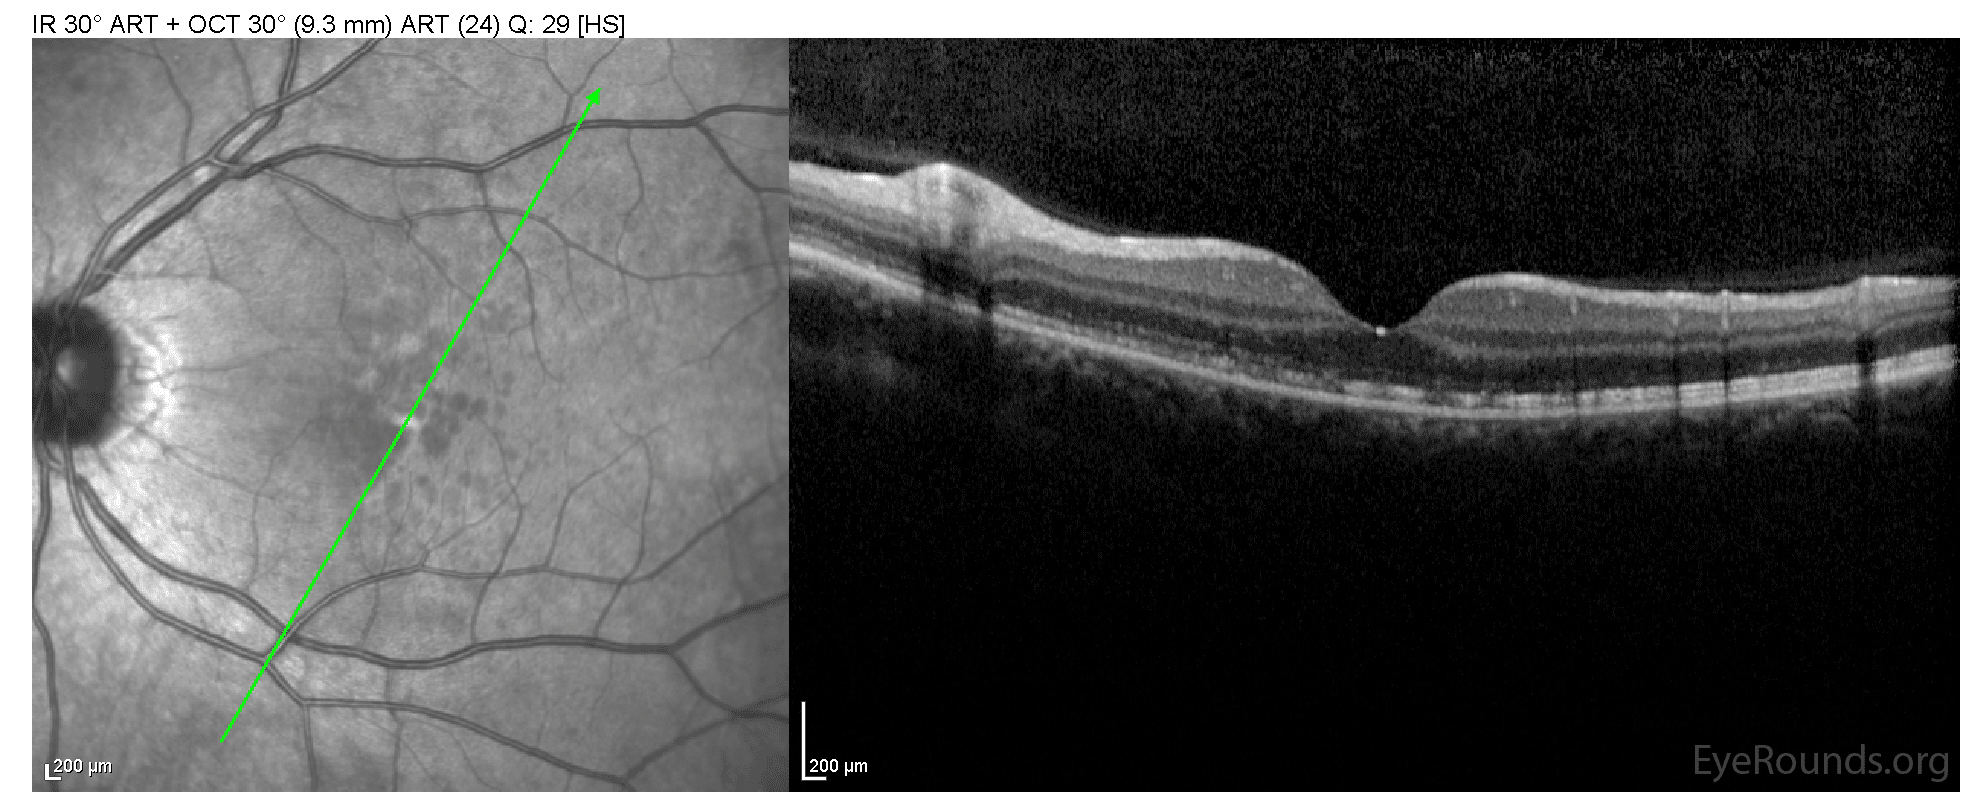

Acute macular neuroretinopathy (AMN) is a rare disease of unknown etiology that most commonly affects young to middle-aged females. The patient typically presents with the acute-onset of one or multiple paracentral scotomas that affect one or both eyes. This is typically the only symptom and visual acuity is unaffected. Fundus findings include 1 or more reddish-brown petalloid perifoveal lesions with the tip pointed toward the fovea that become visible days to months after the onset of symptoms. Lesions are typically better identified with infrared imaging. OCT through the lesions commonly show disruption of the inner segment/outer segment (IS/OS) junction (ellipsoid zone). There is no known treatment and symptoms may not resolve.

44-year-old female with acute onset of paracentral scotomas in right eye (corresponded directly to Amsler grid findings)